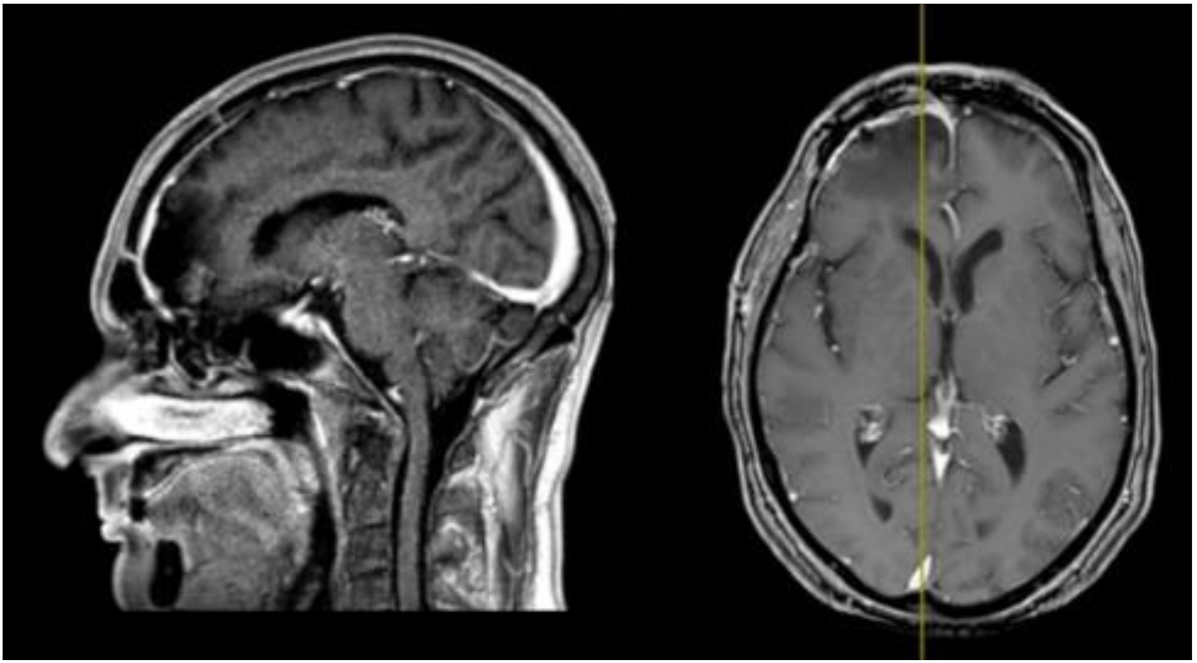

His clinical history started in 2012 with headaches, visual disturbances and behavior’s changes. MRI documented a spheno-ethmoidal lesion with a homogeneous contrast enhancement and with involvement of right anterior skull base (Figure 1). The patient underwent right subfrontal craniotomy with tumor resection. A post-operative MRI showed the apparently complete excision of lesion (Figure 2). Histopathology confirmed the radiological suspicion of meningioma (WHO I). The patient was discharged without complications.

Figure 2.

Post-operative brain MRI T1-weighted with contrast images showing the complete removal of the anterior cranial fossa meningioma.

In 2016 the mass recurred (Figure 3), and a subtotal resection was obtained with removal of superior and middle nasal turbinates and spheno-ethmoidalis planum that was replaced with a titanium mesh. Histopathological exam revealed an atypical meningioma (grade II, WHO 2016). The patient then underwent hypofractionated radiotherapy (30 Gy) for the residual tumor.

Figure 3.

First recurrence of the lesion involving the cribriform plate (T1-weighted with contrast).